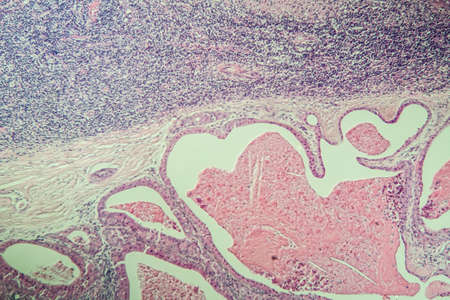

Squamous cell carcinoma of the uterus, light micrograph, photo under microscope